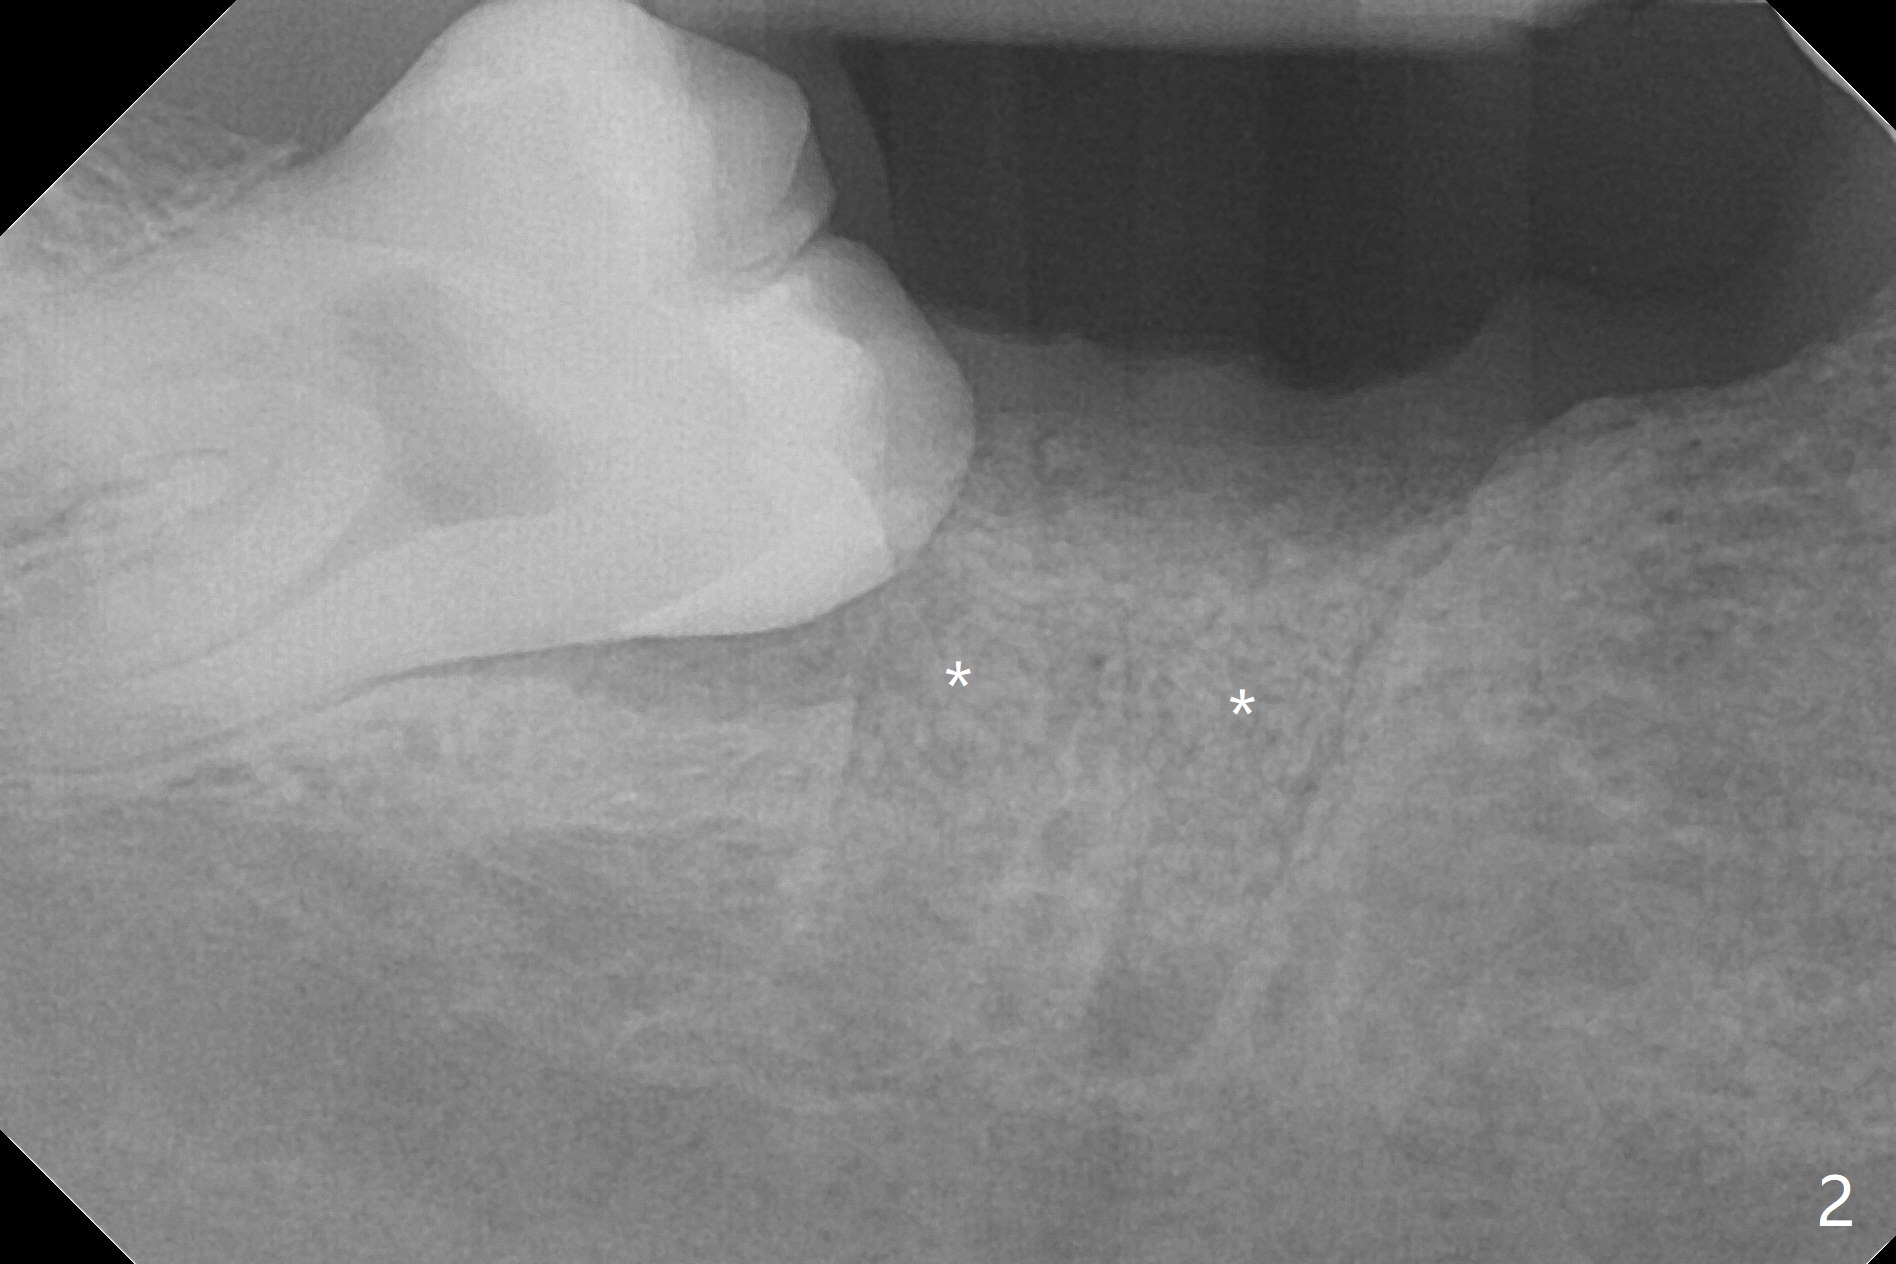

A 50-year-old man requests extraction of the tooth #31 (Fig.1) several months after sedative filling. After placement of Vanilla graft (Fig.2 *) and Osteogen plug, 4-0 Chromic gut suture passes 6-month membrane twice for fixation (figure-8 style), followed by multiple interrupted manner.